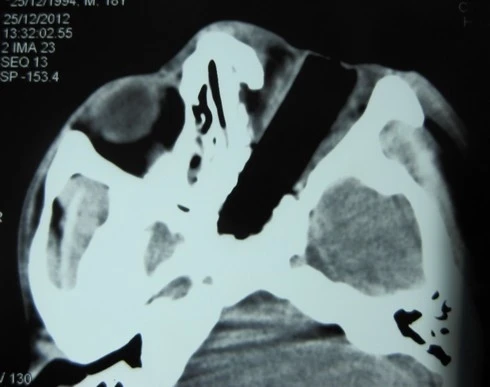

| Ảnh chụp X quang dị vật cắm vào mắt bệnh nhân Chài. |

Bệnh nhân là anh Triệu Văn Chài 18 tuổi, người dân tộc, quê ở huyện Bảo Lâm, tỉnh Cao Bằng. Chiều 22/12, anh đang đi xe máy không may mất lái bị ngã văng vào hàng rào ven đường. Một đoạn que cọc rào đâm thẳng vào mắt trái, gây chảy máu nhiều.

Anh Chài đã được chuyển đến tất cả 7 bệnh viện, từ bệnh viện tuyến huyện đến bệnh viện trung ương, các bác sĩ đều xác định anh bị chấn thương mắt trái rất nặng, mảnh dị vật lớn xuyên thủng nhãn cầu, tổn thương cả cơ vận nhãn và dây thần kinh thị, không có khả năng bảo tồn mắt.

Tại đây, sau ca mổ dài gần 2 tiếng, các bác sĩ lấy ra được một mảnh gỗ dài hơn 4 cm, miếng gỗ gây phá hủy hoàn toàn nhãn cầu, tổn thương xuyên đến các mạch máu lớn…